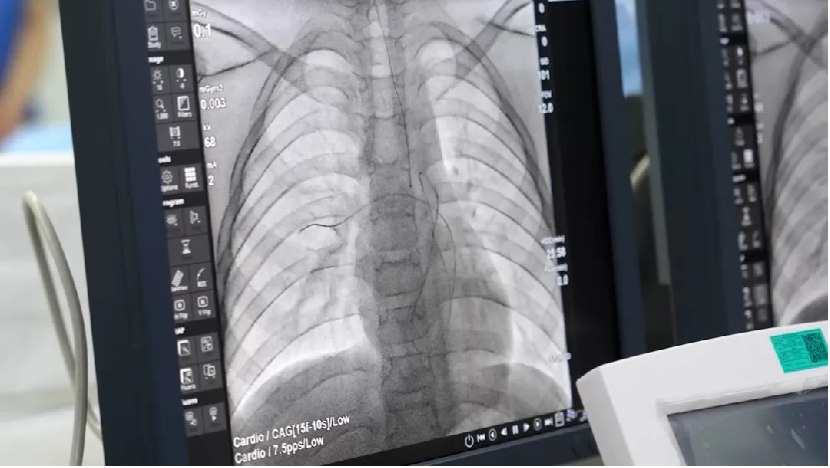

次日,在征得的家属同意后,手术在导管室顺利进行。主刀的是郭保静主任,他经右侧股静脉穿刺,送入MPA导管和圈套器。在X光透视下,发现PICC管末端由入院时胸片显示的右心房漂移至右室流出道。郭保静主任操作这套精密的“渔网”,精准捕捉到那根“潜逃”的导管。

(手术时导管末端飘移至右室流出道)